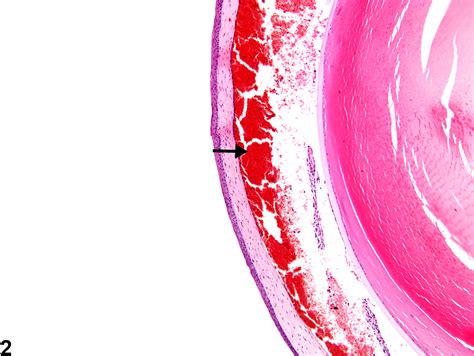

Hyphema

A hyphema is the presence of blood in the anterior chamber, typically resulting from blunt trauma to the eye. This condition requires immediate medical attention, as the presence of blood can significantly spike the internal pressure and cloud the vision.